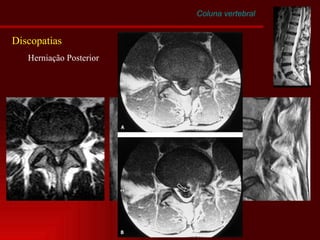

Coluna vertebral Discopatias Herniação Posterior

Coluna vertebral Discopatias Herniação Posterior Migração

Coluna vertebral Discopatias Ruptura do anulo Sequestro